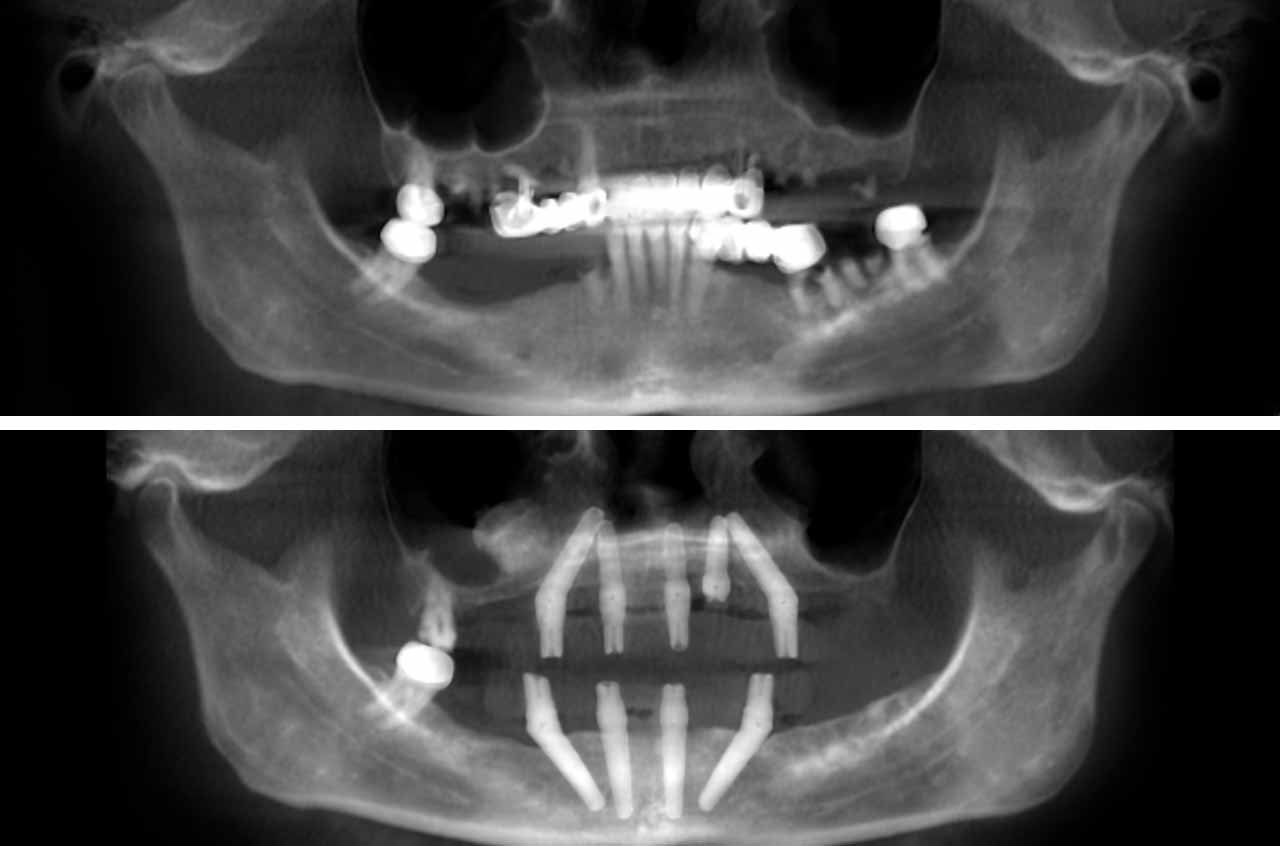

All-on-4 and immediate implant solutions for complete smile restoration. These cases showcase our expertise in full-arch rehabilitation with same-day teeth, providing patients with immediate functional and aesthetic results.

Fewer Implants Needed

Only 4-6 implants per arch, reducing surgical complexity and cost

All-on-4 is a revolutionary dental implant technique that uses just four strategically placed implants to support a full arch of replacement teeth. The posterior implants are angled at 30-45 degrees to maximize bone contact and avoid anatomical structures like the maxillary sinus or inferior alveolar nerve. This innovative approach allows for immediate loading with a temporary prosthesis, providing same-day teeth and eliminating the need for lengthy healing periods between procedures.